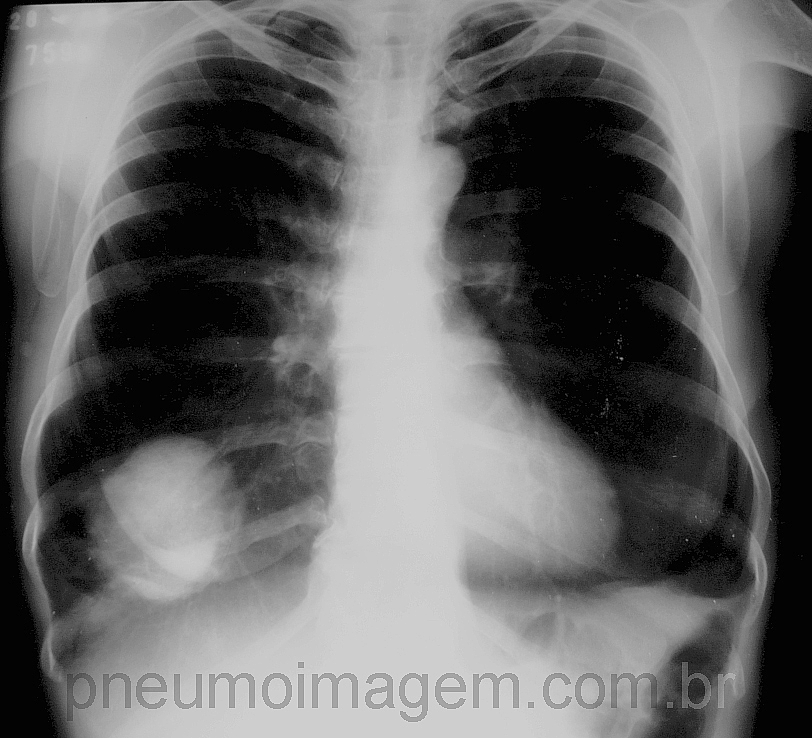

Veja imagens de câncer de pulmão no PneumoImagem, clique aqui.